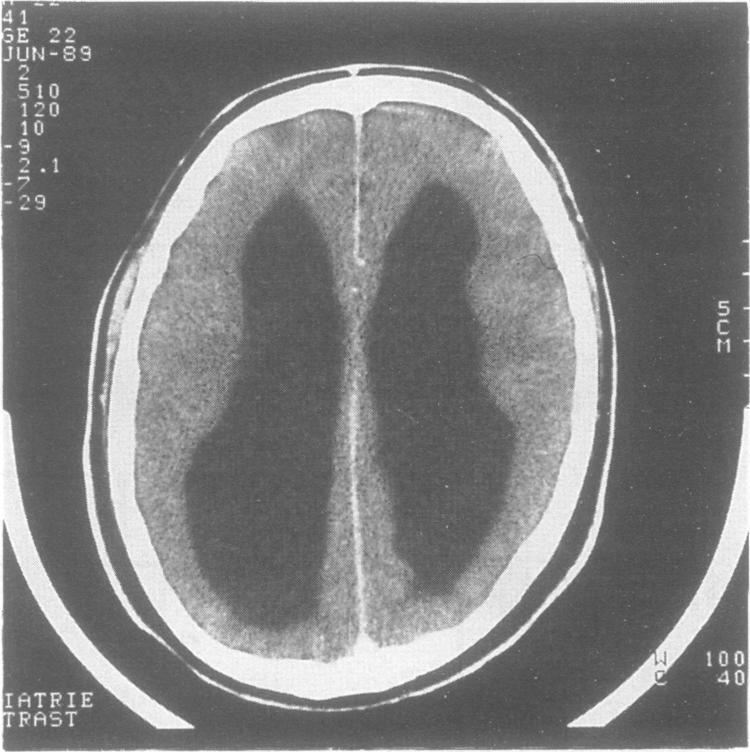

We describe a two generation family in which two males have the X linked recessive MASA syndrome (mental retardation, aphasia, shuffling gait, and adducted thumbs). A third male in this family died at the age of 15 years from congenital hydrocephalus. In the present family cerebral abnormalities are reported for the first time. Linkage analysis confirms the chromosome localisation at Xq28. A crossover between the coagulation factor VIII locus (F8C) and MASA syndrome, but not with DXS52 and DXS305, locates the gene on the same side of F8C as DXS52 and DXS305. The possible relationship between MASA syndrome and X linked hydrocephalus is discussed.

我们描述了一个两代家族,其中两名男性患有X连锁隐性MASA综合征(智力迟钝、失语、拖曳步态和拇指内收)。该家族中的第三名男性在15岁时死于先天性脑积水。在这个家族中首次报告了脑部异常。连锁分析证实了该基因定位于Xq28。凝血因子VIII基因座(F8C)与MASA综合征之间发生了一次交换,但与DXS52和DXS305没有交换,这将该基因定位在与DXS52和DXS305相同的F8C一侧。讨论了MASA综合征与X连锁脑积水之间可能的关系。